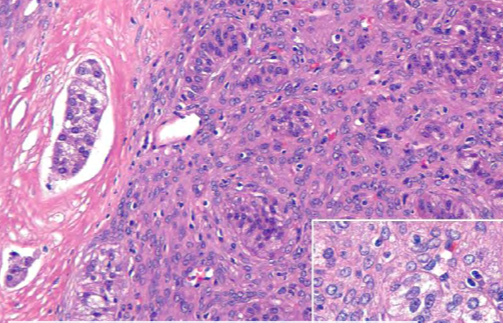

Adrenocortical carcinoma

In dogs, adrenocortical tumors mostly arise from the

In dogs, adrenocortical tumors mostly arise from the zona fasciculata

Many adrenocortical neoplasms are

Many adrenocortical neoplasms are non productive (exact proportion not reported).

Roughly 50% benign/malig; Around 10% bilateral.